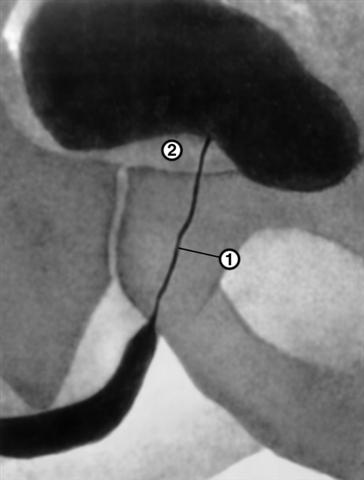

Восходящая уретроцистограмма

Рис. 2. Восходящая уретроцистограмма при аденоме предстательной железы: 1 — суженная предстательная часть уретры; 2 — дефект наполнения мочевого пузыря, обусловленный увеличенной предстательной железой.